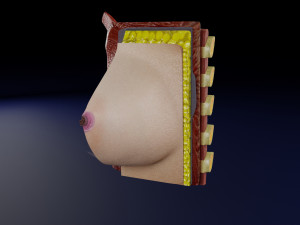

This is a 1:1 scaled model of right breast cut opened in sagittal plane to reveal its internal antomy and histology (schematic). The deeper parts and fascial layers are also depicted to give a very detailed approach to the model. The full layers starting from skin, nipple areola, till intercodtal muscles and ribs are also depicted.